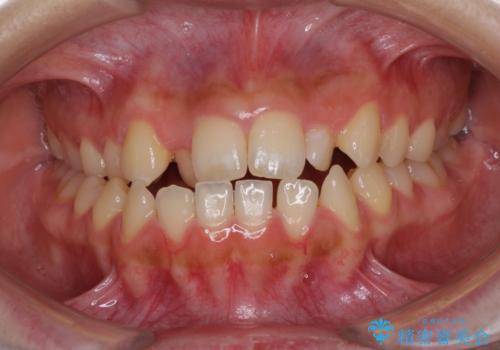

- 前歯のデコボコと、下顎の変位と受け口を気にして来院された患者様です。

初診時には大学病院にて顎の骨を切る外科矯正を勧めましたが、妥協的なゴールでも構わないので外科処置をせずに矯正を行いたいとのことでした。

まずは急速拡大装置にて上顎骨を側方に拡大し、インビザラインにて歯列と咬合を整えることとしました。

上顎骨を拡大したことで、下顎の歯列を上顎が受け入れられるようになりましたが、インビザラインでは咬み合わせを改善させることができなかったため、ワイヤー矯正にて仕上げることとしました。

ワイヤーを使用したものの、上下前歯のオープンバイトがなかなか改善されませんでしたが、患者希望により治療終了となりました。